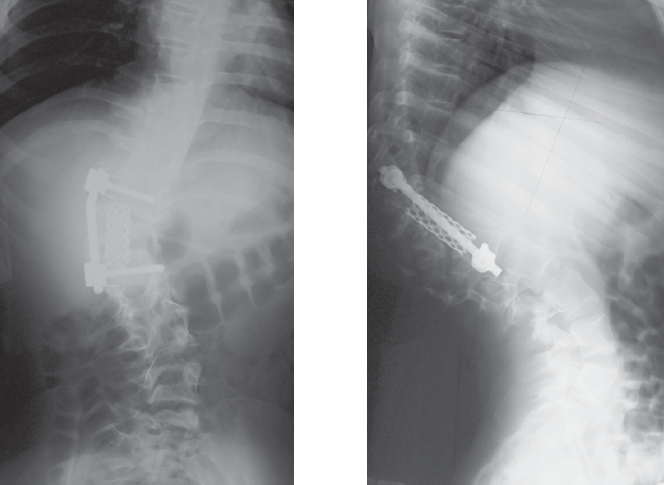

Неврологического дефицита нет (Frankel E). При магнитно-резонансной томографии данных за компрессионную миелопатию не получено. При компьютерной томографии (рис. 1) определить природу порока развития затруднительно в связи с выраженными вторичными изменениями смежных сегментов. Для анализа представлены рентгенограммы, выполненные в раннем возрасте (5 месяцев, 1 год 7 месяцев; рис. 2, 3).

Рис. 1. Компьютерная томография при обращении (возраст 12 лет)